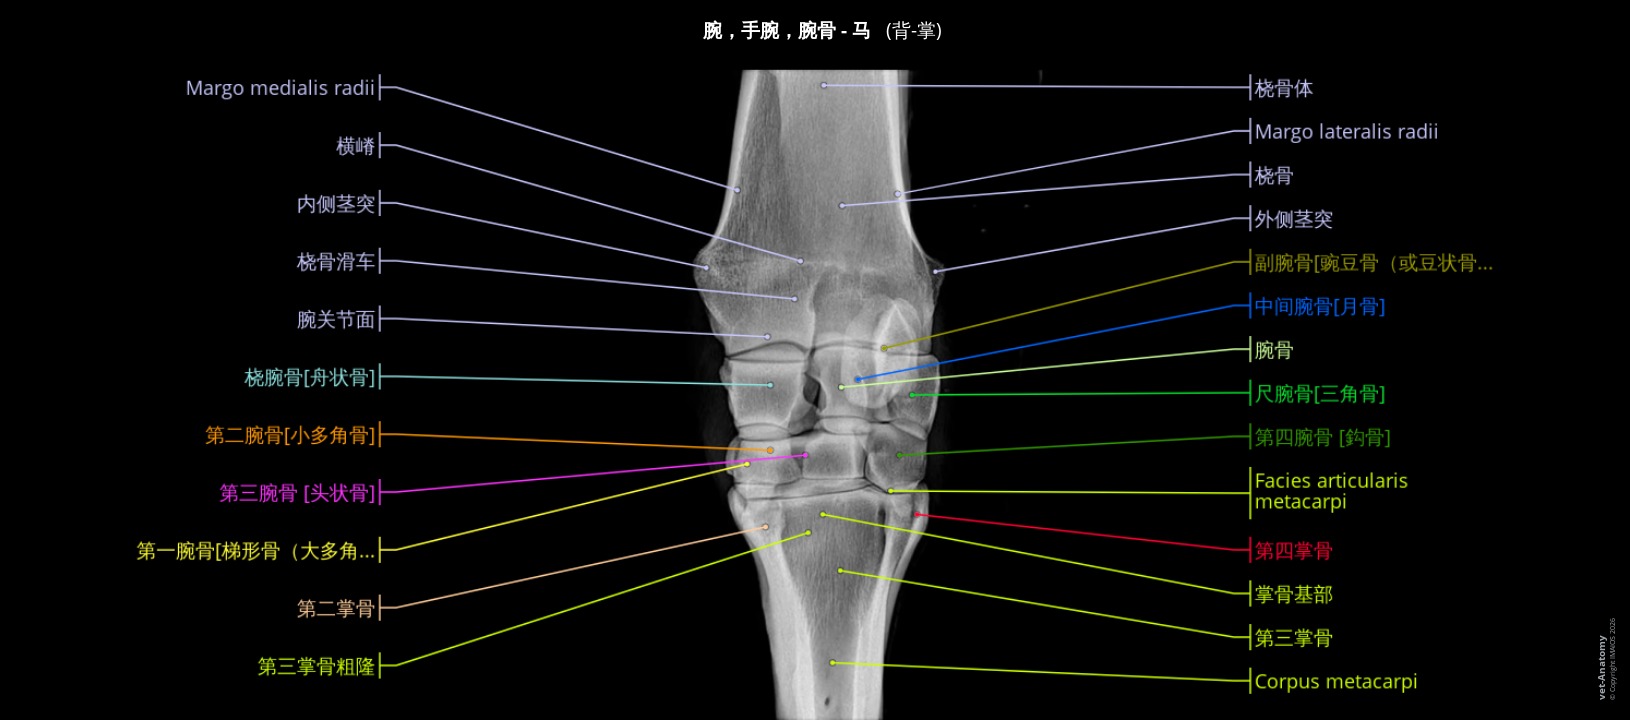

放射照相是常用于马匹的成像方式,特别是在出售或跛行诊断时:如结合超声检查,甚至CT和MRI,它可以准确和早期诊断病变,特别是骨关节病。

解读放射线图像必需有良好的解剖学知识。此单元是为学生、兽医从业者和放射科医生提供关于成年马的正常放射学解剖基本信息。

材料与方法

这些放射检查采用最常见的发病情况,由法国南特Vétérinaire Oniris大学医院中心医学影像高级讲师Marion Fusellier和医学影像技术员Carla Bouillaut所进行。此外,Susanne Boroffka博士dipl.

ECVDI(荷兰乌特勒支大学)和Sébastien Caure博士(法国Saint Michel de Livet的Vétérinaire équin de Livet医院中心)提供了一些检查。

解剖部分由Stephan Mahler, MA, MSc, PhD (IMAIOS的兽医解剖学家)根据国际兽医解剖学名词(NAV)进行标注。标签只限于临床感兴趣的主要结构,并按不同的主题组织。